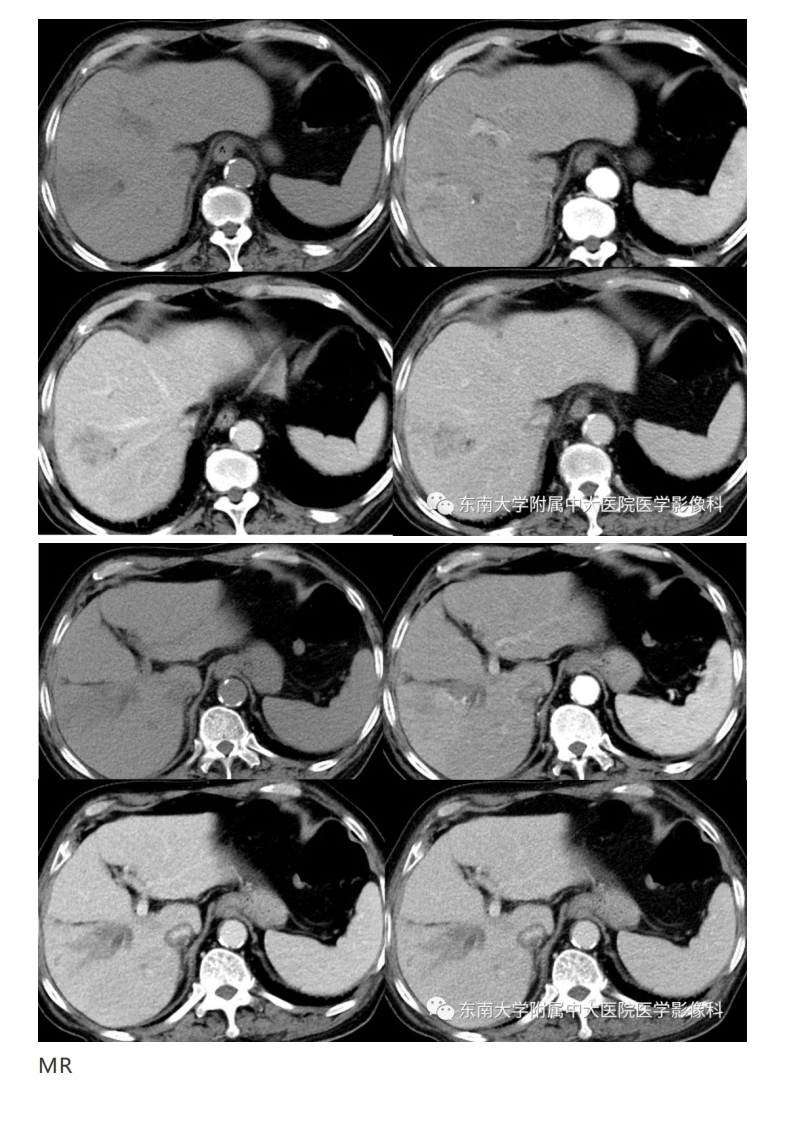

20191230_2【晨读结果公布】2019.12.30消化系统疾病.pdf